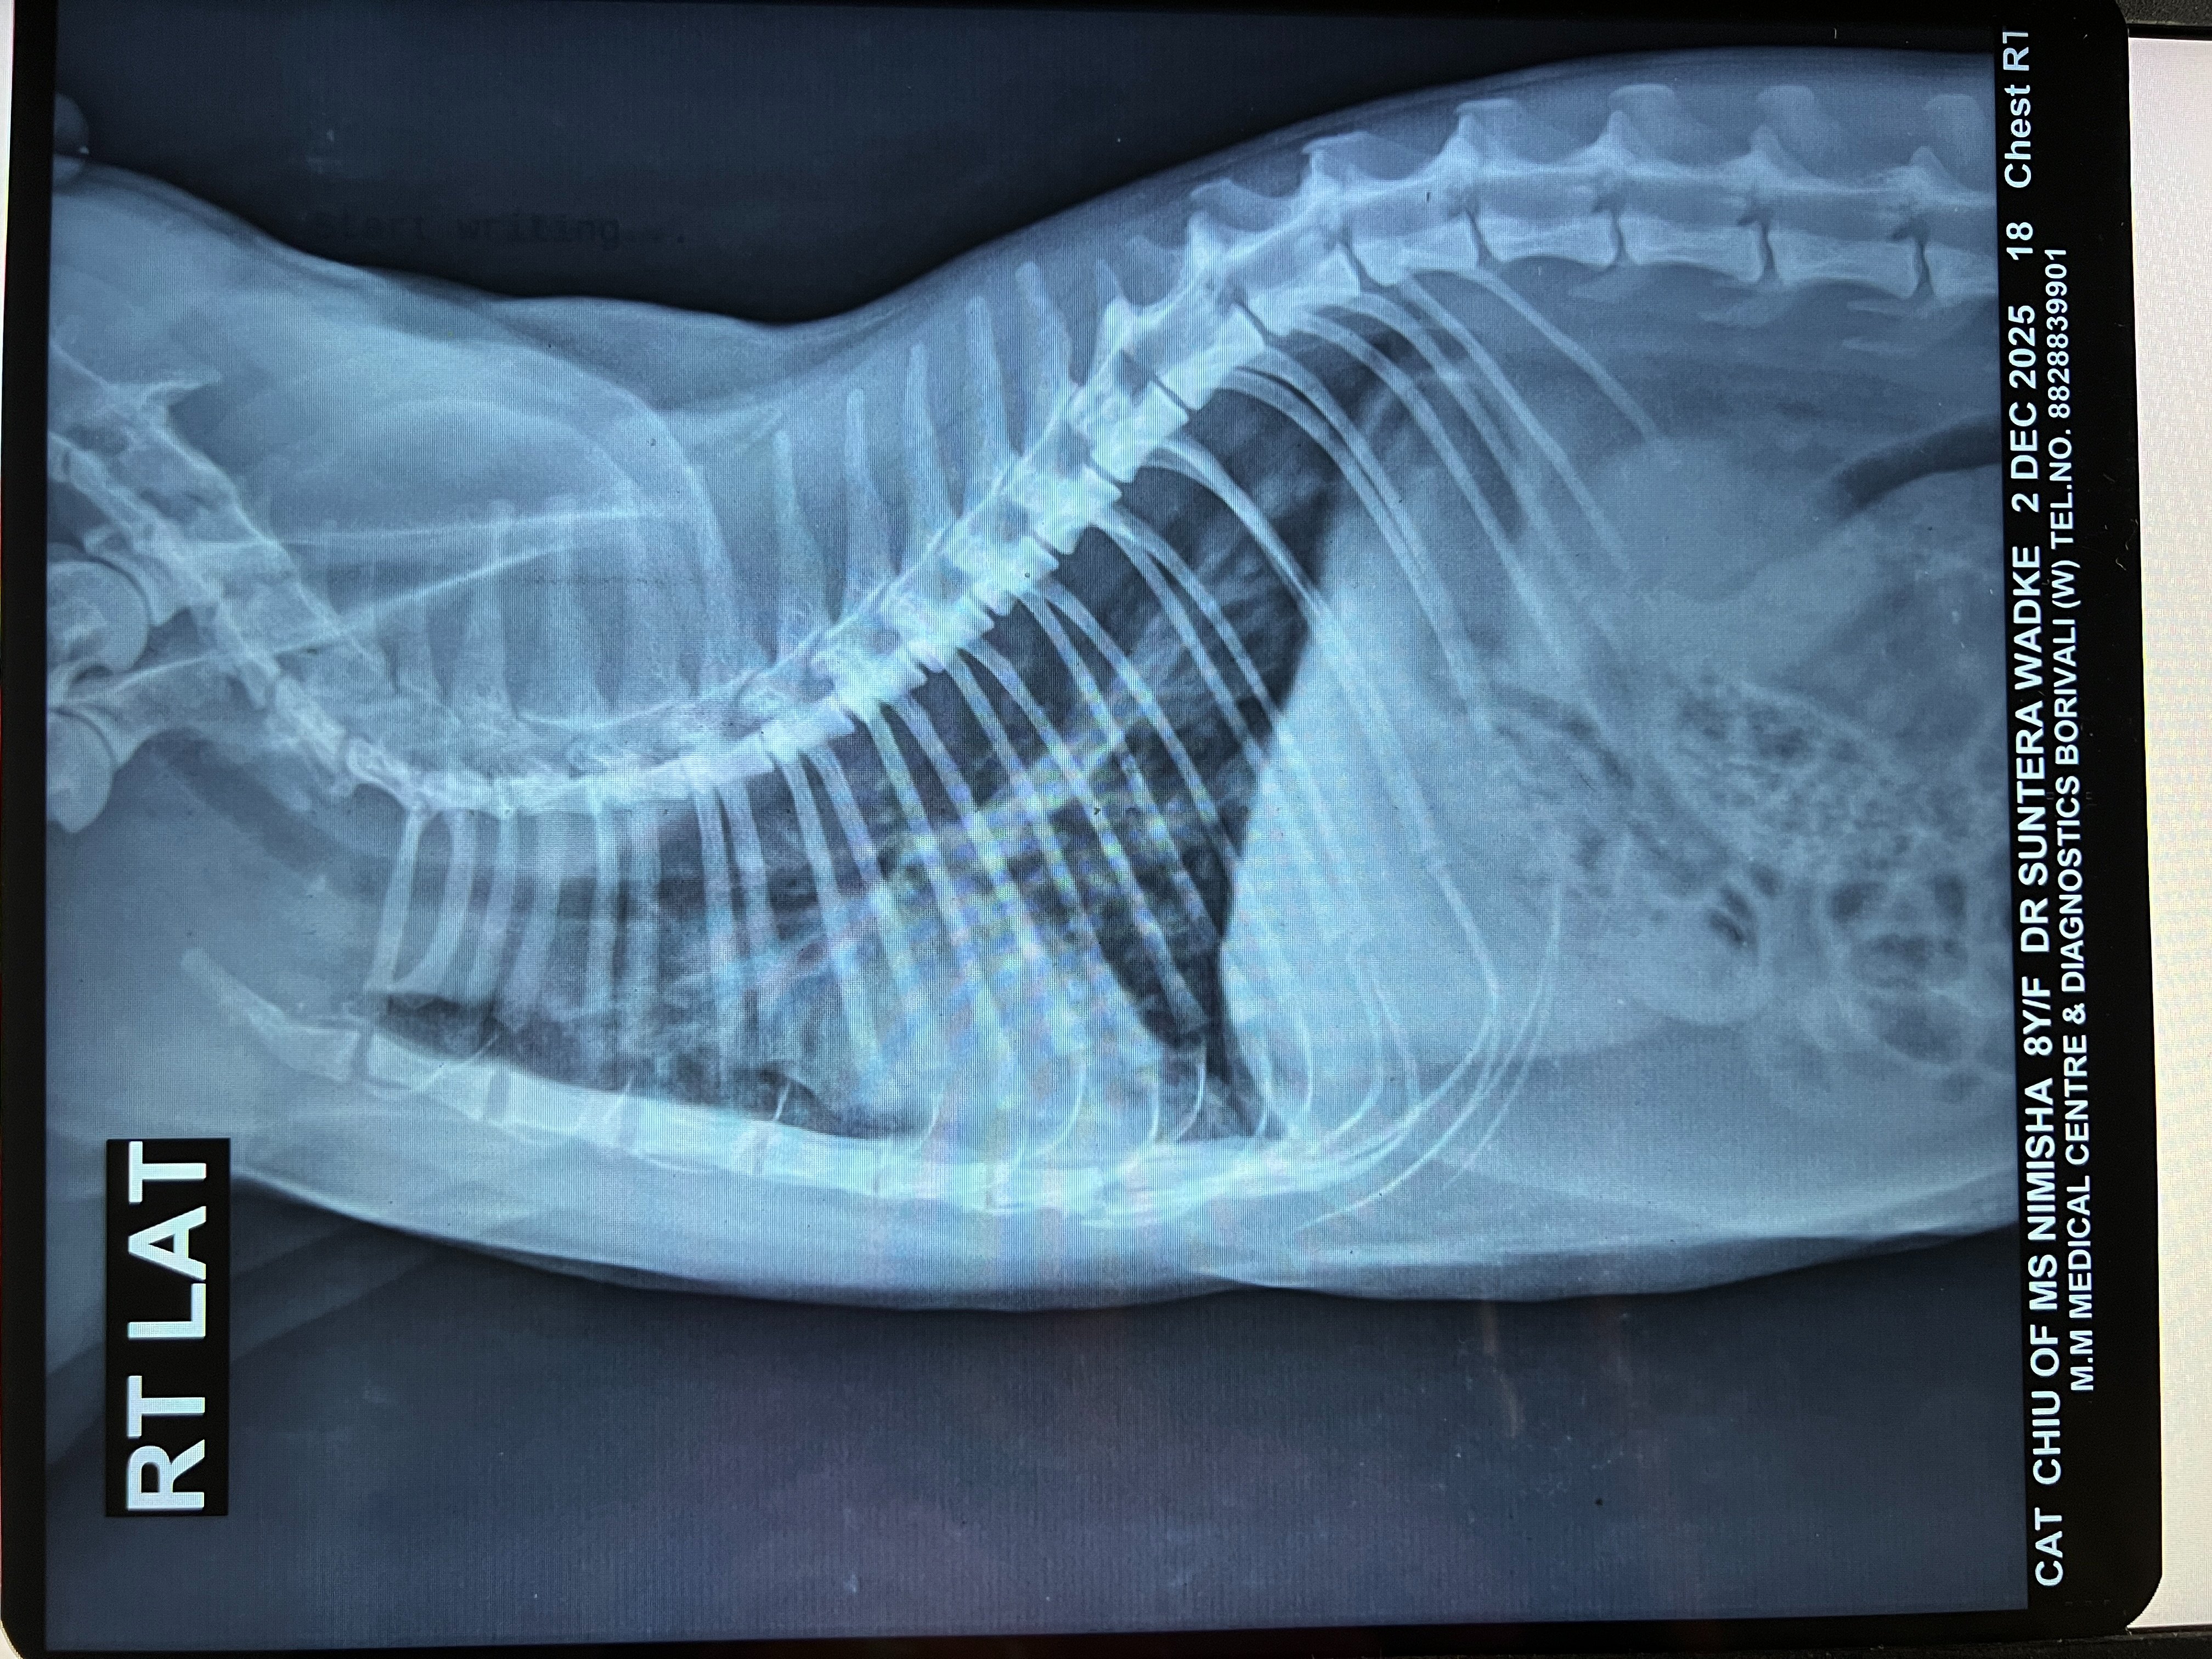

In early August, we got a repeat x-ray (attached) done which still showed bronchial lung pattern. She got Lasix and Penetrat (similar to Frenzyme). She stayed ok for about a month before symptoms returned.

3.1 Xray - RT LAT - Chiu - 02Dec2025.jpeg2.4 MB · Views: 41 -